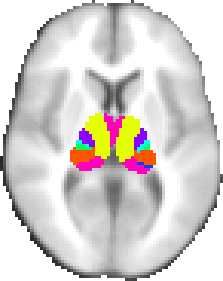

Oxford thalamic connectivity atlas

A probabilistic atlas of 7 sub-thalamic regions, segmented according to their white-matter connectivity to cortical areas, kindly provided by Heidi Johansen-Berg and Timothy Behrens, FMRIB.

This connectivity atlas reports probability of anatomical connection from points in the thalamus to each of 7 cortical zones. These probabilties are calculated using probabilistic diffusion tractography in multiple subjects. For more details see the Thalamic Connectivity Atlas web page.